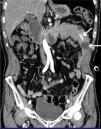

En la exploración física, el catéter Foley provisional estaba migrado distalmente, y la movilización, rotación e intentos de retiro de la sonda, exacerbaban el dolor abdominal. En la tomografía computarizada (TC) se observó el catéter Foley migrado en yeyuno proximal, con datos tempranos de isquemia intestinal (figs. 1 y 2). Se realizó cirugía de urgencia encontrando una intususcepción a 50 centímetros del ángulo de Treitz, secundaria a la migración del catéter Foley.

La intususcepción yeyunal secundaria a la migración pospilorica del catéter de gastrostomía es una complicación rara relacionada con el uso de sondas de gastrostomía que carecen de un punto de fijación externo en pacientes con peristalsis normal, lo cual favorece la migración distal del catéter4-9. Se ha formulado la hipótesis de que el intento de retirar la sonda mientras el globo está inflado podría ser un factor contribuyente al desarrollo de la intususcepción7. Los clásicos signos de «diana», «dona» y «forma de salchicha» observados en TC son útiles para diagnosticar esta complicación3,4. De igual manera, los signos de migración distal de sonda de gastrostomía, incluida la incapacidad de retirar la sonda, pueden estar asociados con dolor abdominal y síntomas de obstrucción al tracto de salida gástrica. La ictericia obstructiva transitoria puede presentarse cuando el catéter migra a la segunda parte del duodeno8.